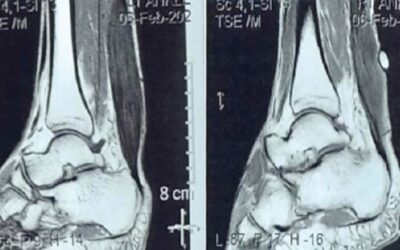

Non-Unions of the Hind Foot

Hind foot non-unions are a complex orthopedic challenge that clinicians face, particularly due to the unique anatomy and weight-bearing responsibilities of this part of the foot. Non-unions occur when a fracture fails to heal nine months after injury or shows no radiographic improvement over a consecutive 3-month period. This condition is not only painful but can also severely impact mobility and quality of life.